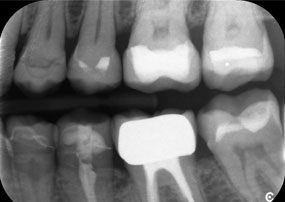

A second case highlighting the clinical capabilities of the Power Edition involved the replacement of a damaged zirconia crown in a 63-year-old patient. The patient presented with a chipped veneer on her 20-year-old zirconia crown on tooth 6. Despite the posterior location, the patient found the defect bothersome and requested a new restoration.

The Power Edition enabled precise sectioning, with the increased torque and enhanced cooling contributing to the controlled removal of the crown without significant material loss. The chucking system and enhanced torque proved to be essential in this process.